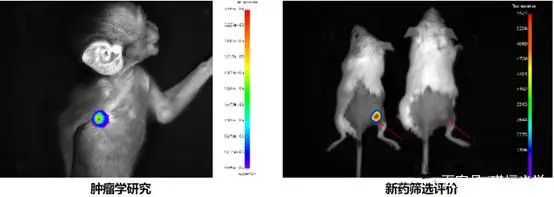

利用一套非常灵敏的光学检测仪器,让研究人员能够直接监控活体生物体内的细胞活动和基因行为。通过这个系统,可以观测活体动物体内肿瘤的生长及转移、感染性疾病发展过程、特定基因的表达等生物学过程。